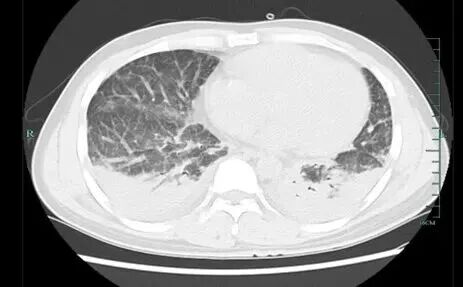

壮哥经检查:胸部CT双肺弥漫性病灶,血氧饱和度指标不到70%。“重症肺炎,I型呼吸衰竭。再拖下去有生命危险!”他随即被安排住院治疗,并做了基因检测,揪出了真凶——马尔尼菲篮状菌。

壮哥的肺部情况

经过抗真菌等一系列治疗后,壮哥的呼吸衰竭症状明显改善,胸部CT复查也显示病灶明显吸收好转。如今,他已经临床治愈,带药出院回家进行巩固治疗。